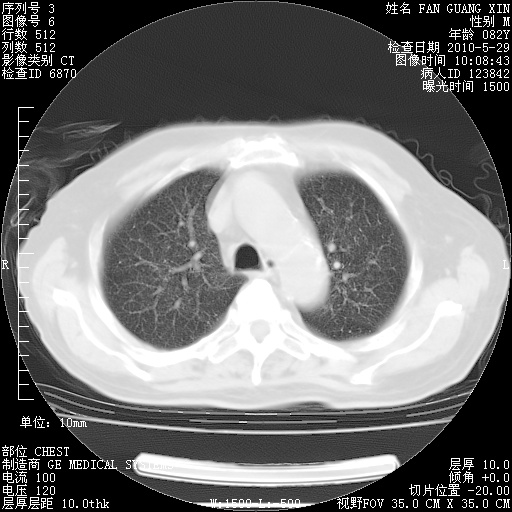

还需要哪些辅助检查?我们医院排除真菌感染没有任何检验方法,胸片好像能够排除肺部真菌感染。